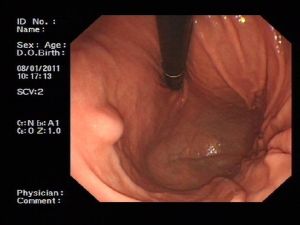

5.胃鏡檢查 普通內鏡可以直觀腔內型腫瘤的形態大小及生長特點,亦可直接行組織活檢以取得病理學證據,甚至可經胃鏡行胃平滑肌瘤摘除術但對於沒有侵犯黏膜的腫瘤及腔外型腫瘤則意義不大可見半球形或球形隆起,表面黏膜 緊張光滑,色澤與周圍黏膜相同,頂部有時可出現缺血壞死性潰瘍術前確診較困難,常需要組織學檢查才能證實。